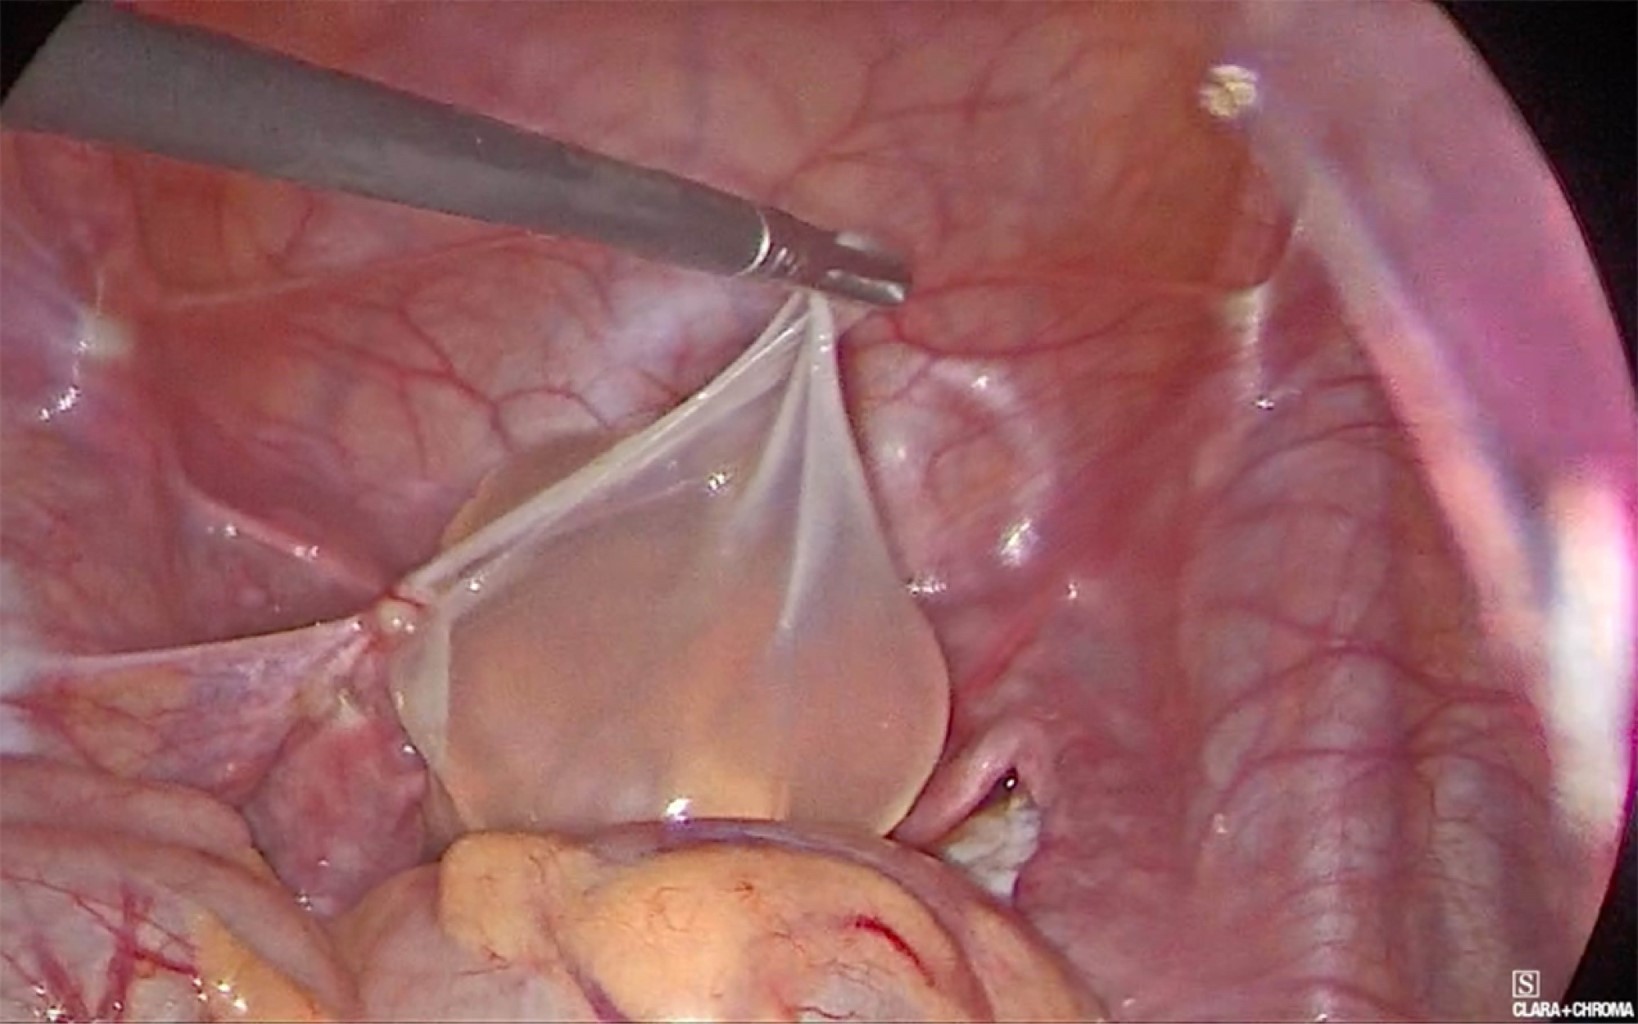

Se colocó trocar umbilical de 10 mm con lente de 30 grados, dos más de 5 mm en ambas fosas iliacas, encontrando en pelvis cuatro quistes de diferentes tamaños, siendo el mayor de 12 cm aproximadamente, otros de 7, 5 y 4 cm, con paredes delgadas y lisas, traslucidos, con contenido líquido seroso, dos sueltos en pelvis (Figuras 3 y 4) y dos adheridos ligeramente a ovario y trompa izquierda, retirados con bisturí armónico (Figura 5). Se puncionó con aguja, extrayendo de cada uno líquido seroso para estudio histopatológico y citoquímico. Se extrajeron las cápsulas en su totalidad; ovarios y útero, así como el resto de la cavidad sin alteraciones, se tomó biopsia de peritoneo y epiplón mayor. Se lavó pelvis y revisó hemostasia. La paciente cursó con evolución favorable, egresando a las 24 horas del procedimiento.

A nivel macroscópico los quistes en el MPMB pueden ser uniloculares o multiloculares; flotan libremente en la cavidad abdominal o se adhieren a las estructuras peritoneales, varían de 1 mm hasta 20 cm, se agrupan y forman masas similares a uvas en la cavidad peritoneal, por lo general contienen líquido transparente o hemorrágico.2

La cirugía es la opción definitiva para el diagnóstico y tratamiento, la laparoscopía es el abordaje de elección, se busca la resección completa de los quistes visibles; siendo posible la asociación con un tratamiento adyuvante como la peritonectomía y tratamiento citorreductor (HIPEC) para eliminar la evidencia de enfermedad microscópica, logrando periodos libres de recurrencia a 10 años hasta en 79% de los pacientes. Al tratarse de una patología que se presenta principalmente en mujeres en edad reproductiva, es importante evitar las estrategias agresivas que puedan tener repercusión en la fertilidad.1,7,10 La terapia hormonal con agonistas de la hormona liberadora de gonadotropina y agentes antiestrogénicos, como el tamoxifeno, son útiles para el tratamiento y la prevención de las recidivas debido a la asociación con receptores hormonales para estrógenos y progesterona en algunos tumores.9